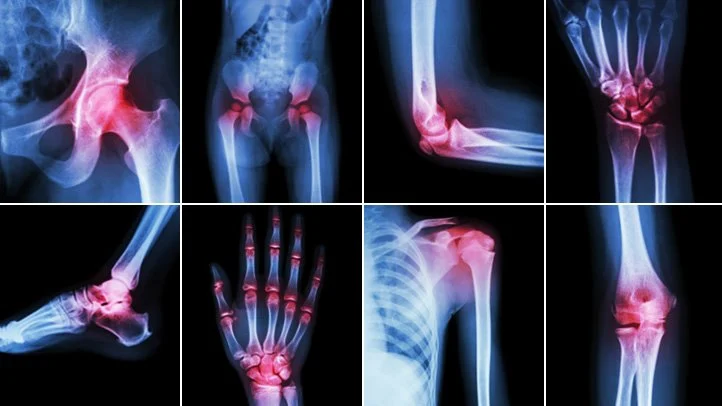

Arthritis affects millions of people all over the world. In fact, from the year 2010 – 2012, approximately 52.5 million adults (22.7%) in the United States were diagnosed with some form of arthritis. Unfortunately, this number is projected to reach 78 million (26%) by the year 2040. Aside from this, arthritis is also considered as one of the leading causes of disability attributed to work limitation and increased risk of falls and injuries (Centers for Disease Control and Prevention, 2016).

For people diagnosed with arthritis, pain is generally categorized as chronic that usually lasts for at least three months. Many patients describe this type of pain as aching, dull, burning or throbbing, which is comparable to a boa constrictor squeezing the affected joints. However, though arthritis can be well-managed by different treatment options, pain can also be sudden and unpredictable. This acute episode of pain and inflammation, referred to as arthritis flare, is oftentimes triggered by infection or stress. Though acute arthritic pain is only temporary, it can significantly affect our everyday life in terms of our capacity to perform daily tasks.